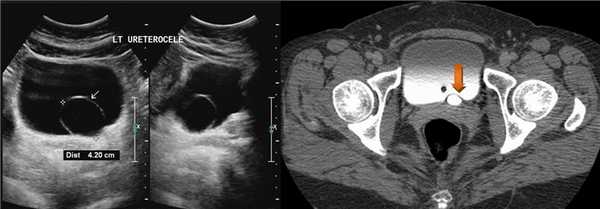

Уретероцеле на УЗИ

На УЗИ в мочевом пузыре или в уретре определяется анэхогенное образование, округлой формы, с четким и ровным контуром; соответствующий мочеточник обычно заметно расширен; может присутствовать гидронефроз верхней части удвоенной почки. Уретероцеле определяют как внутрипузырные (полностью внутри мочевого пузыря) или внепузырные (некоторая часть постоянно расположена в шейке мочевого пузыря или в уретре).

Рисунок. Уретероцеле (стрелка) на УЗИ и КТ.